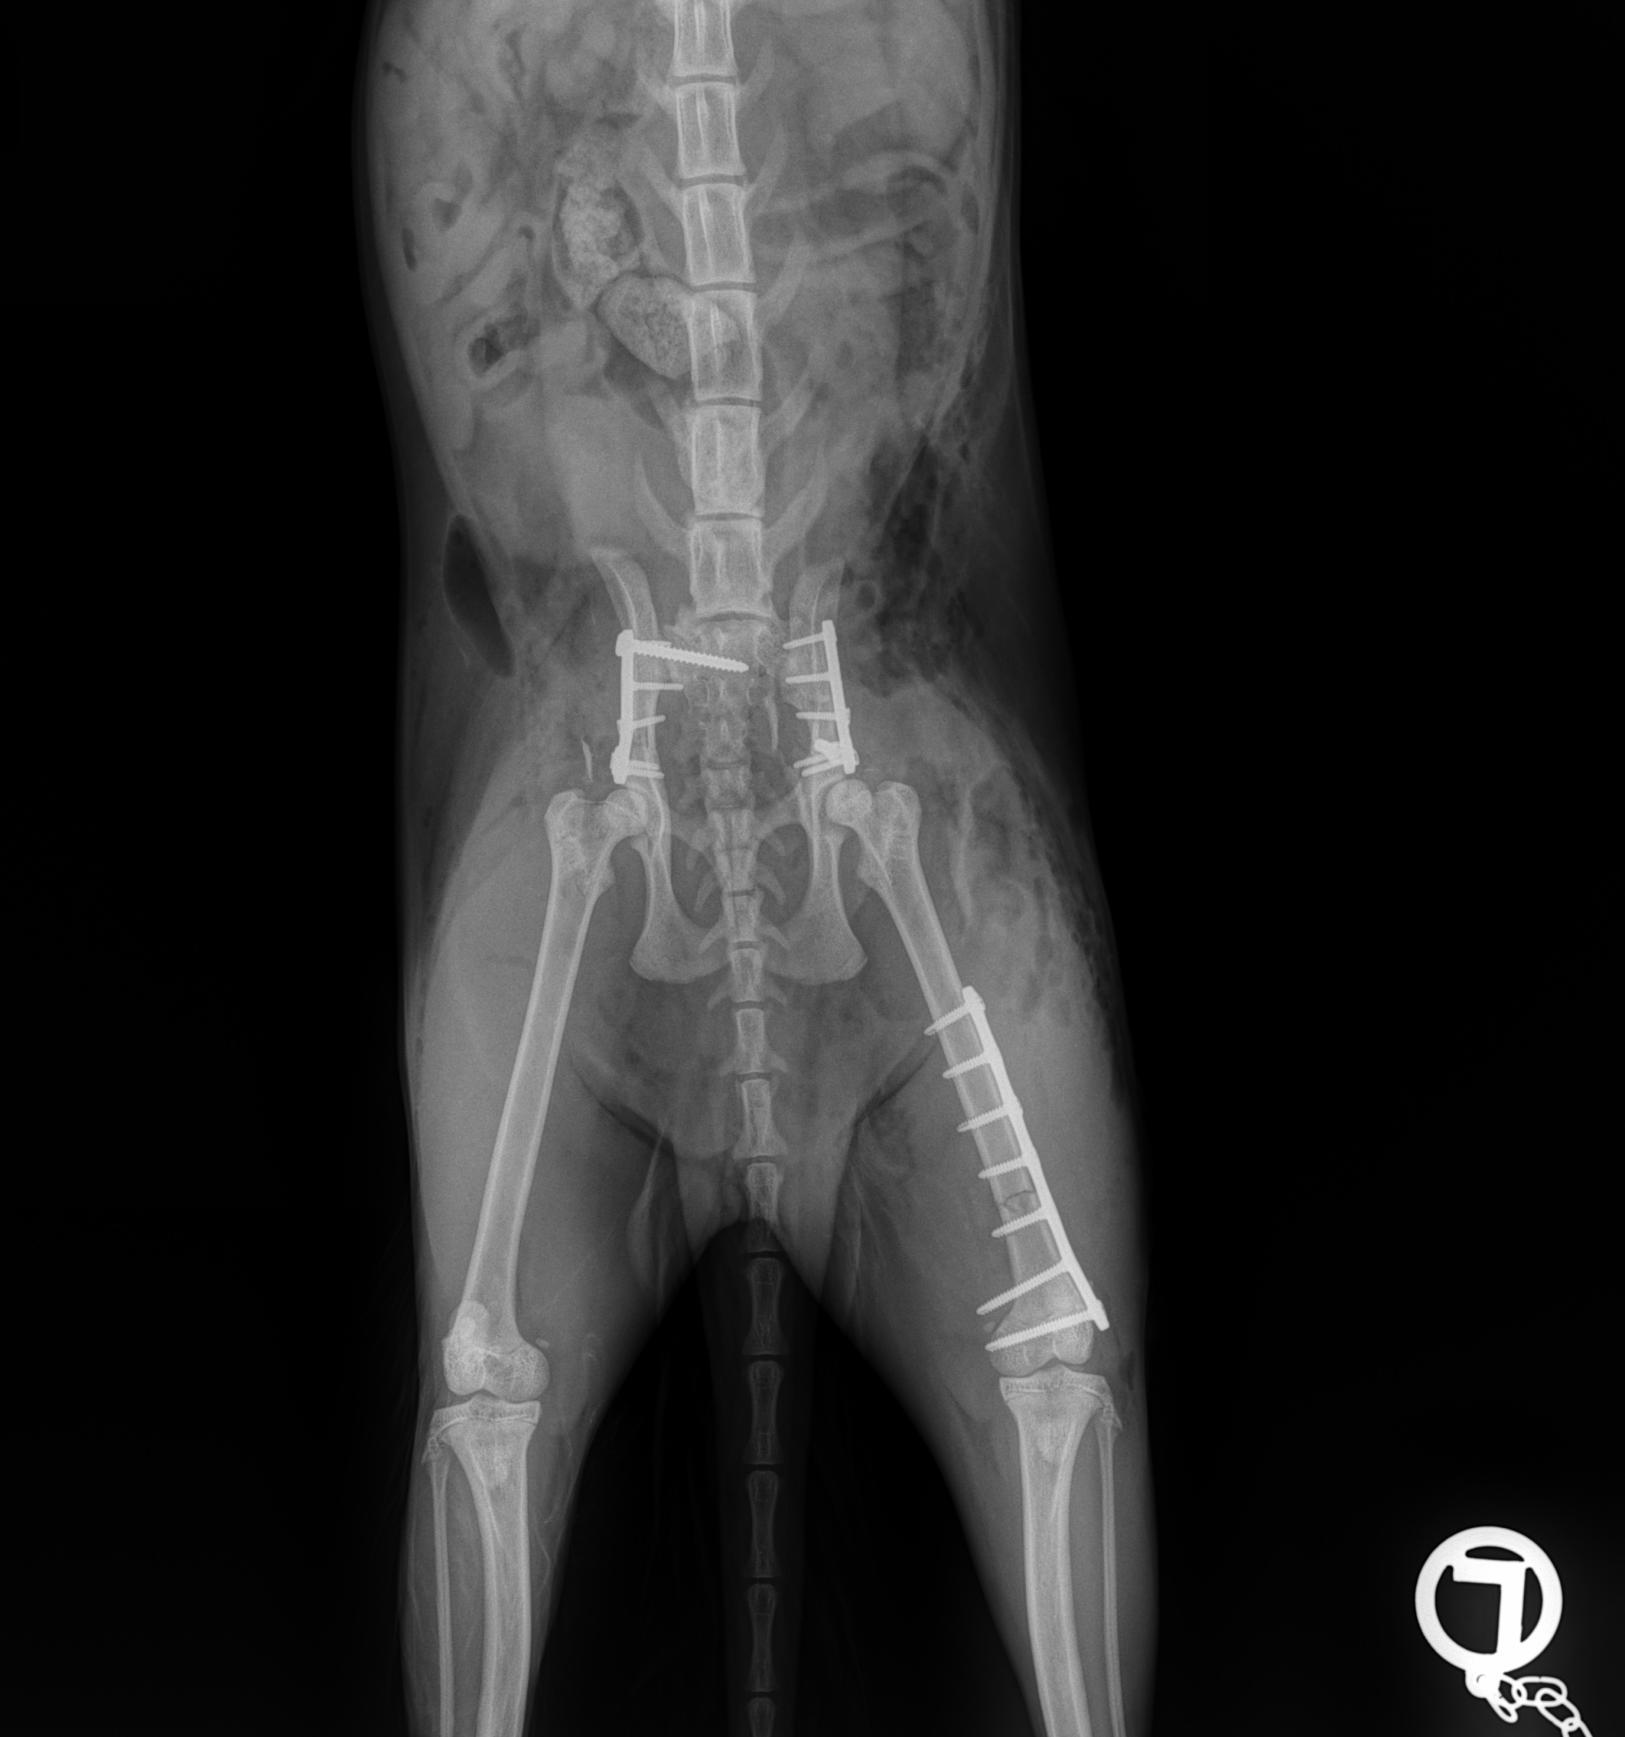

Fracture Treatment in Small Breeds:

Experience of 100 Cases

CrCL Ruptures in Small Breeds:

Osteotomies or extra capsular repair

CrCL Ruptures in Small Breeds: Should we use osteotomies instead of extra capsular repair?

TTA RAPID®

Learn how to perform CCL Repair with TTA RAPID®

Tiny TTA RAPID®

Learn how to fix CCL Ruptures in Tiny Animals with the Tiny TTA RAPID® System

Rapid Luxation

Learn how to fix Patella Luxation with the RAPID LUXATION System